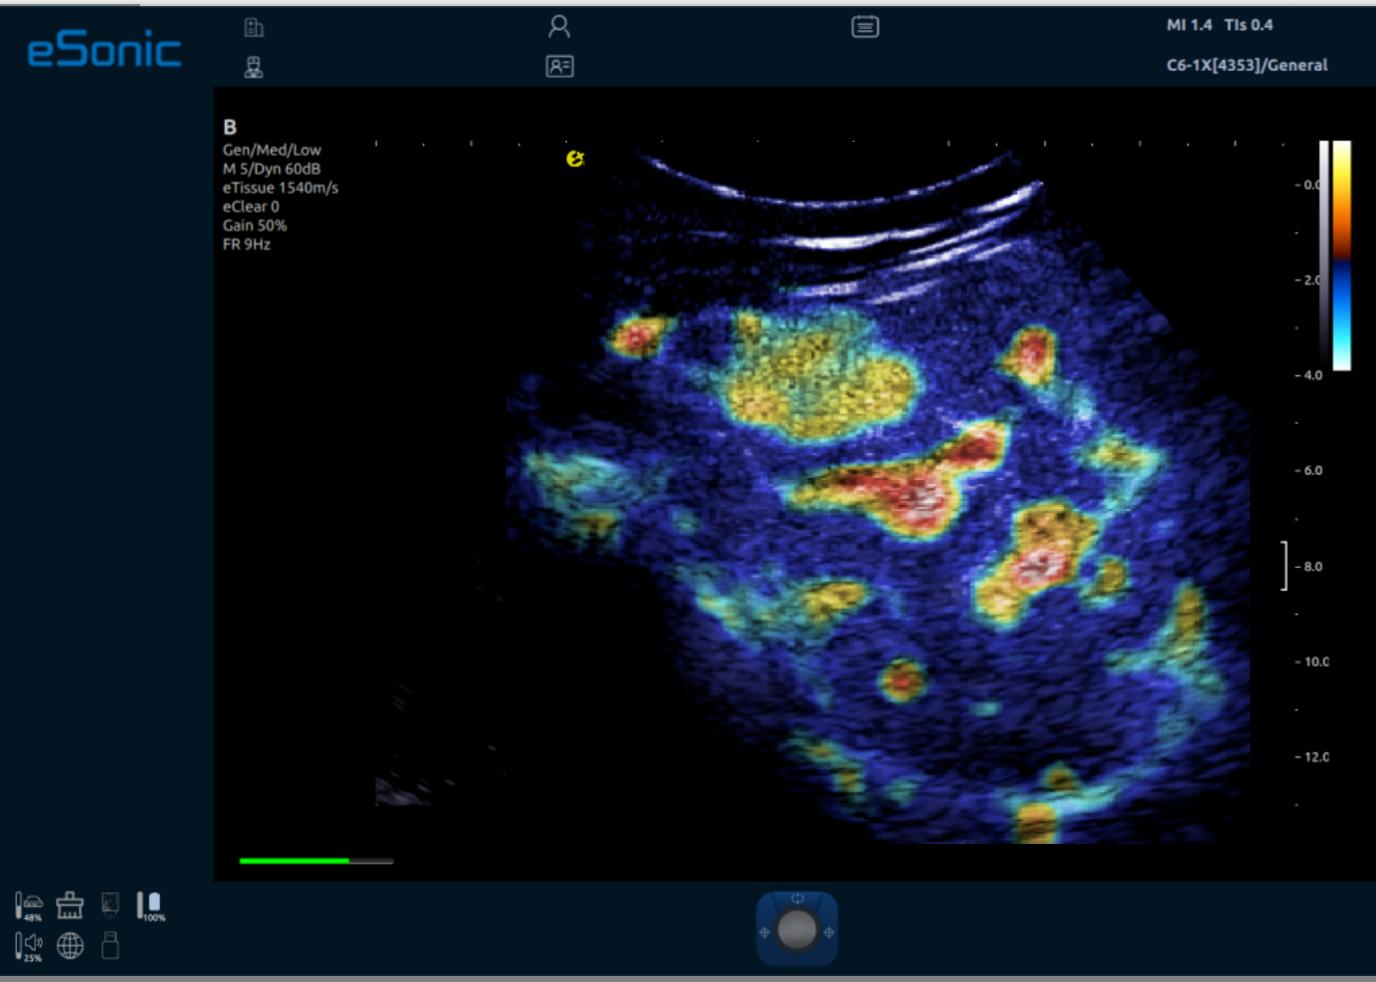

iPlane Vascular 微视血流显像-小鼠大脑皮层

iPlane Vascular 微视血流显像